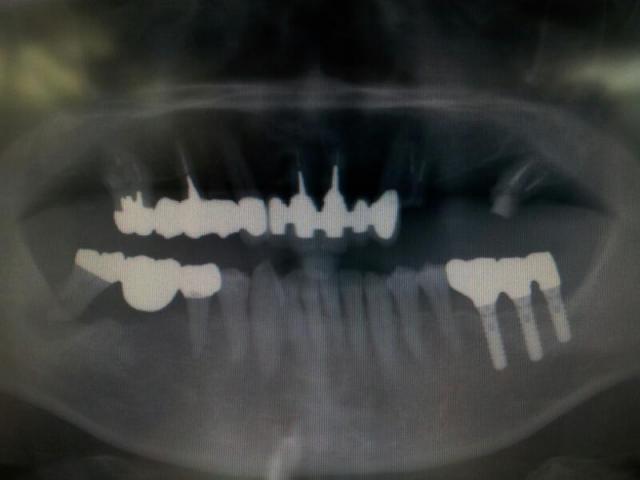

今日、本当に久しぶりにいらした患者さんは当時の私が手掛けた究極の

症例だった。しかし、19年経過した今では変わり果てた状態でいらした。5年に1回程度悪くなったときにしか来てくれない方だ。

私が開業する前の平成5年に

インプラントを始めてから3例目ぐらいの患者さんで

症例に使われた

インプラントは当時はITI

インプラント充実型スクリュータイプというネーミングであったが現在は

ストローマンインプラントスタンダードタイプというネーミングに変わっている。

経過19年の

症例を出せる先生はあまりいないだろう。この

症例では奇跡的に

インプラントは無傷であるがブリッジが年を追うにつれて崩壊していったことがわかるだろう。

インプラントの対合歯もブリッジであったがそちらが崩壊して

インプラントは無傷だったのだろう。もうひとつ奇跡的に助かったのは今、使用している

インプラントは審美目的でマージン部が骨に近い位置に設定されているが当時のものは2.8ミリでマイクロギャップが歯肉縁上であったことも原因であろう。

左上と右下は現在、左下は数年前